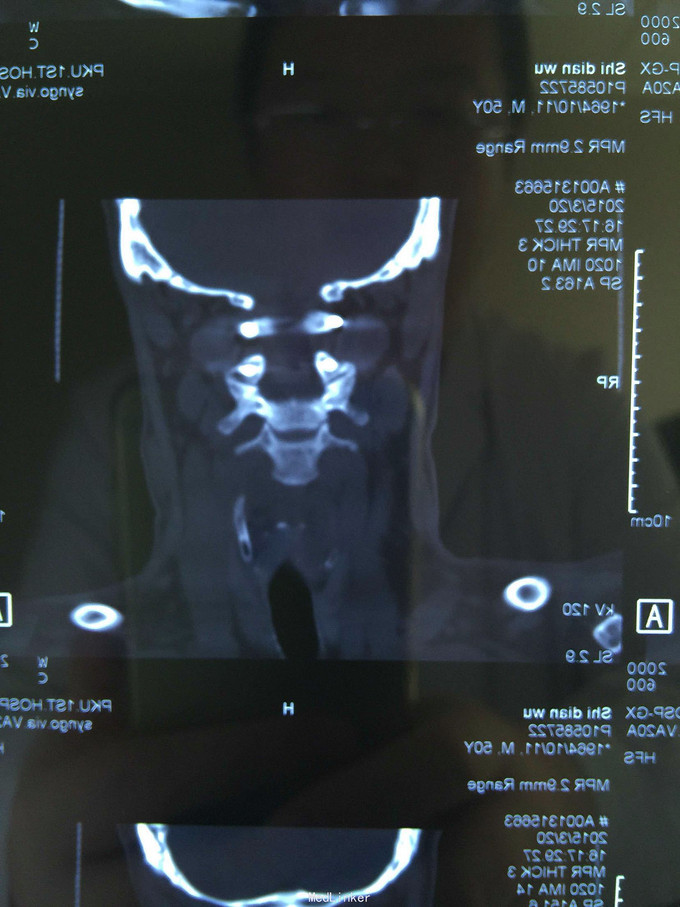

颈部活动受限,双上肢肩关节外展肌力3-,屈肘3-,伸腕3-,屈指2-,伴双上肢感觉过敏。下肢伸膝3-,屈髋2-,hoffman(+),巴氏征(+)。x片现实c1/2脱位,,MRI提示C2齿状突骨折,移位,压迫脊髓

C2齿状突骨折伴C1/2脱位。考虑C2齿状突粉碎性骨折,难以从前路行齿状突骨折复位固定,因此先行颅骨牵引下复位,9kg牵引后复位良好,行后路C1-2椎弓跟钉固定,植骨融合术,术后颈托固定,症状术后缓解良好。

术后3个月,6个月随访,颈部疼痛已消失,肌力恢复良好,返回工作岗位。术后6个月核磁及ct提示,颈椎序列恢复,脊髓无受压,椎弓根钉位置良好。 讨论:上颈椎损伤致瘫率高,应尽早手术治疗,椎弓根钉固定安全,有效,坚固,是有效的治疗方法。